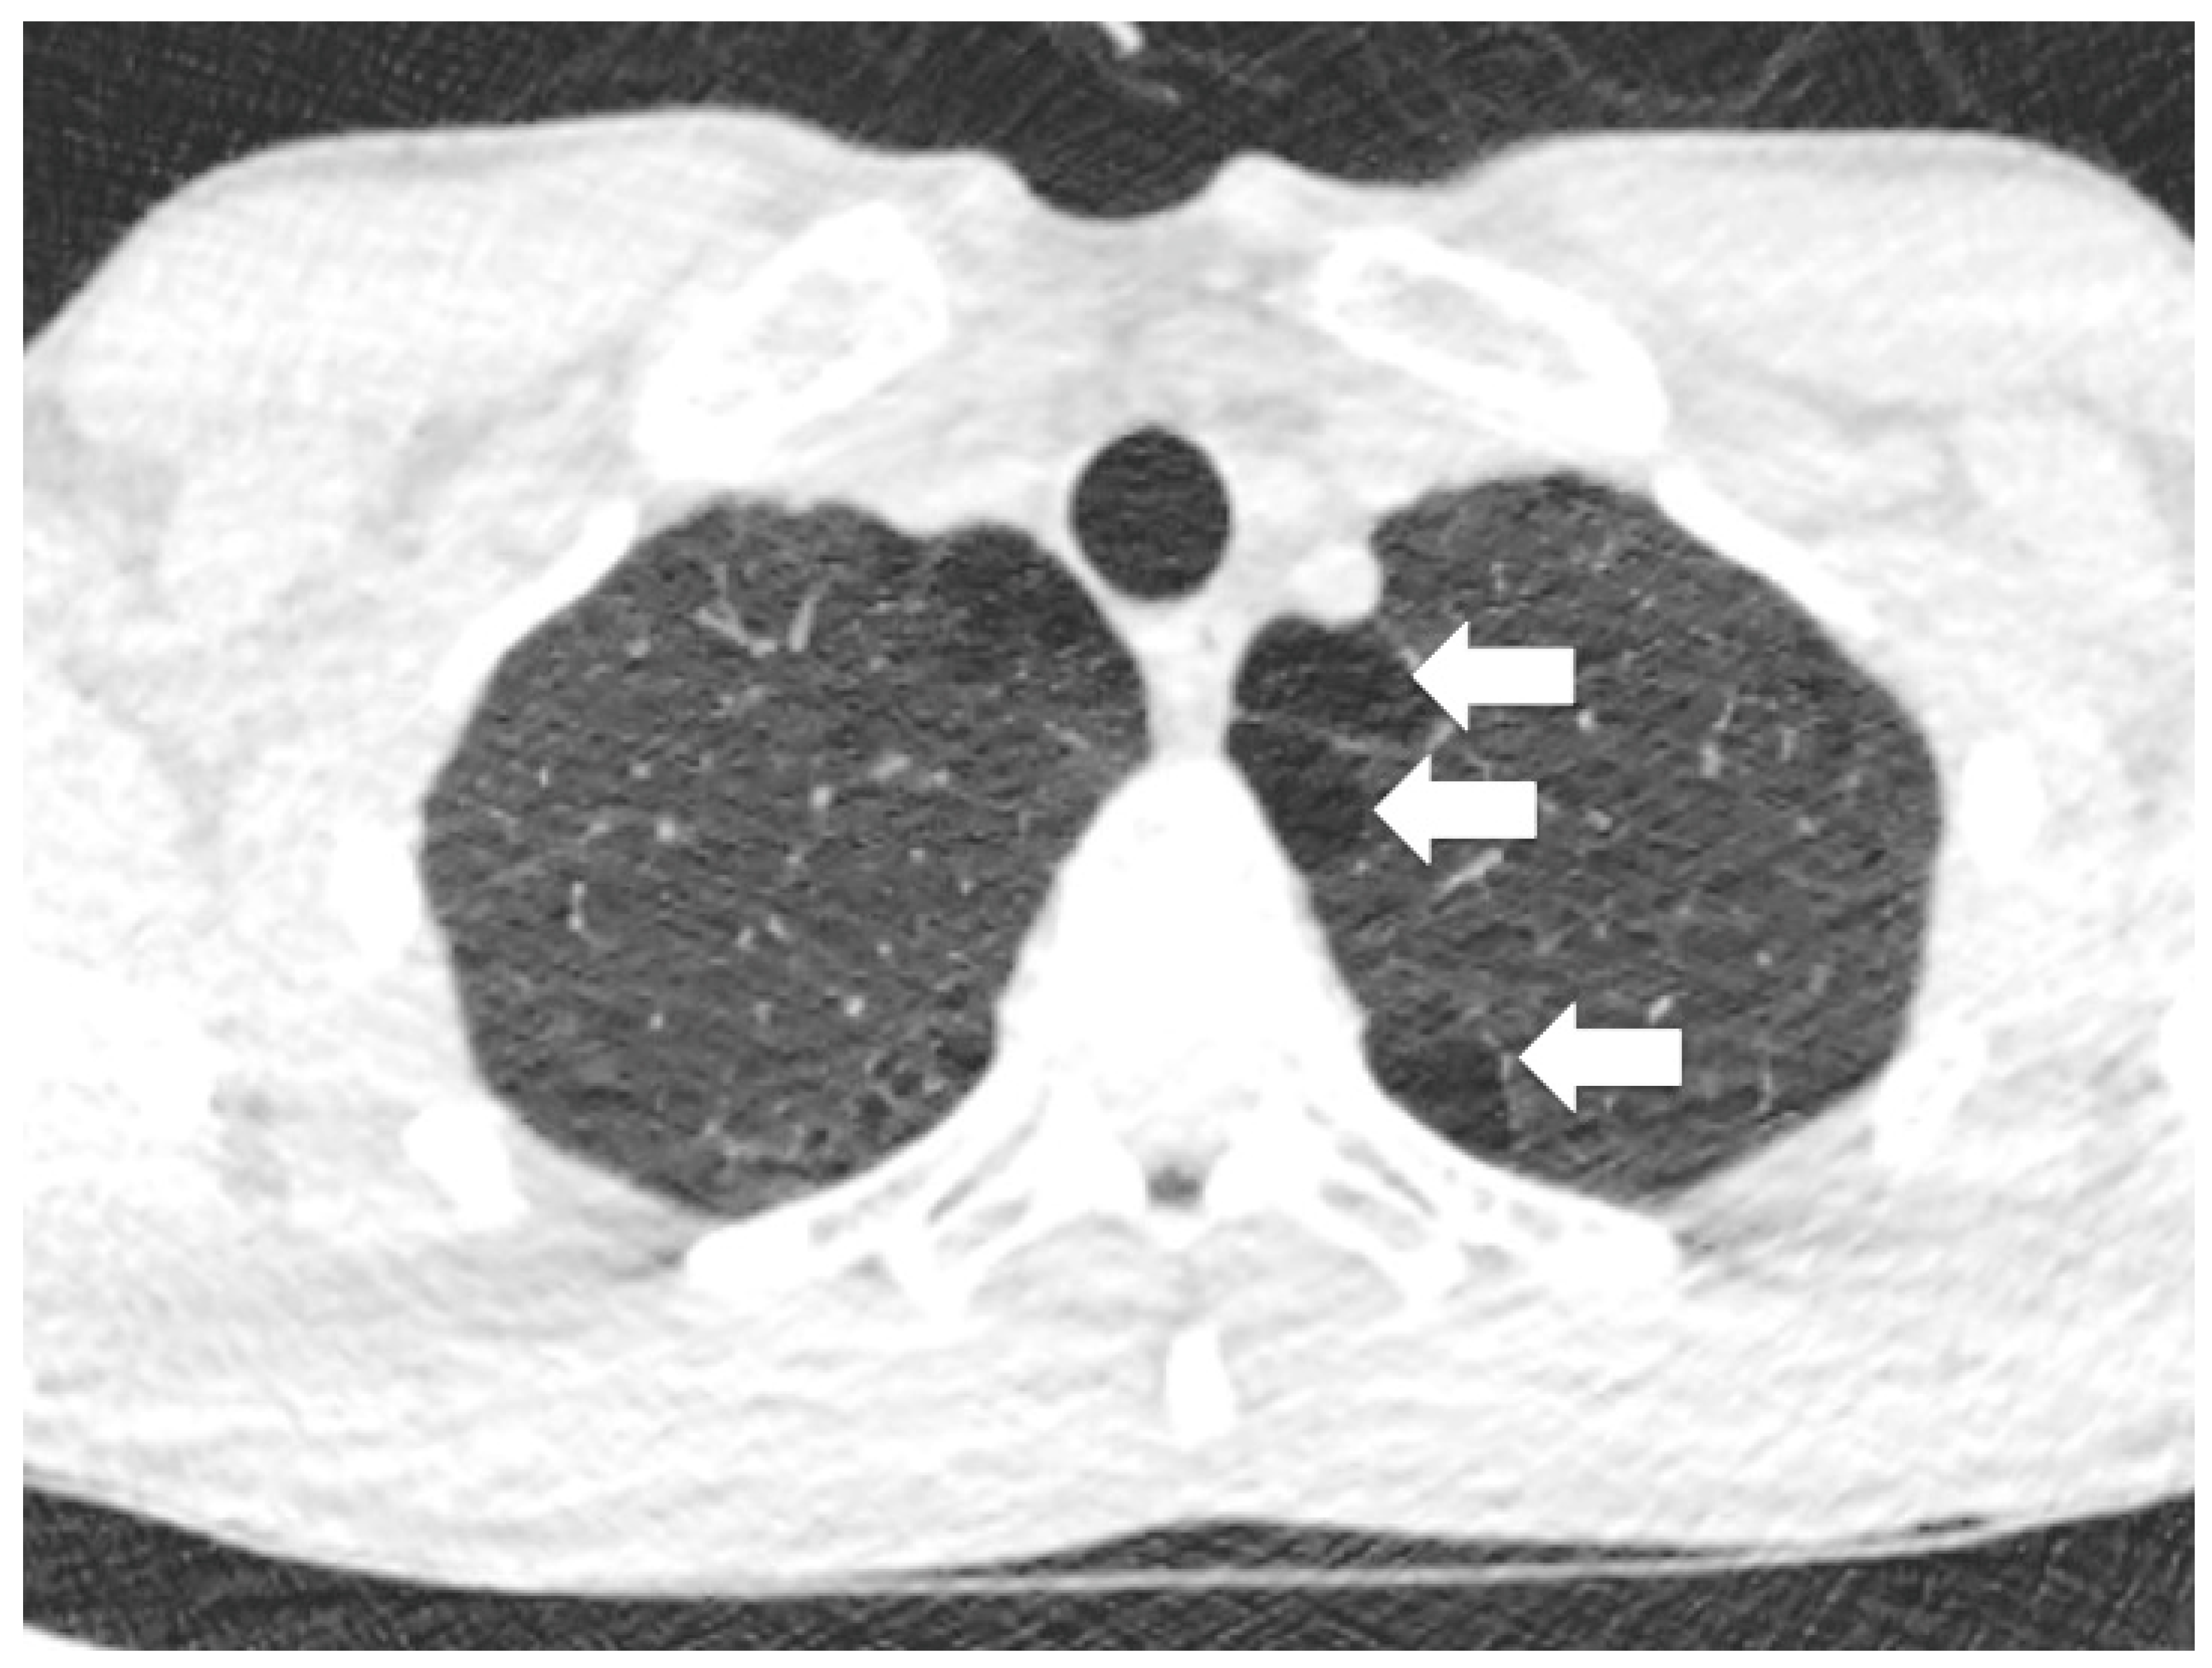

2.3. Abnormal Underlying Lung

2.4. Blebs and Bullae